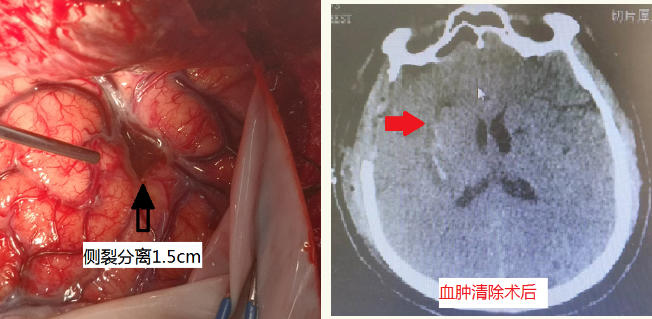

患者病情危急,经绿色通道急诊入神经外科。入院诊断:右侧基底节脑出血,应激性溃疡。王宝庆副主任接诊病人后迅速完善术前各项准备,急诊手术治疗。考虑病人年轻,保留神经功能至关重要,手术采取显微镜下分离脑组织自然间隙作为入路清除血肿的方式进行,血肿完全清除,术中分离脑组织时几乎是不出血的,副损伤降到最低。